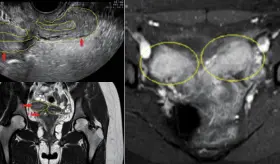

La mujer de 71 años, con antecedentes de histerectomía total y salpingooforectomía izquierda hace 30 años, presentó distensión abdominal progresiva y aumento de peso durante cuatro años.

Los lipomas uterinos son tumores benignos poco frecuentes cuya histogénesis aún es incierta. Debido a su rareza y a los hallazgos radiológicos inespecíficos, suelen confundirse con leiomiomas o incluso con tumores malignos.